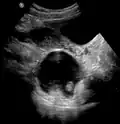

A complex cyst due to a dermoid as seen on ultrasound -